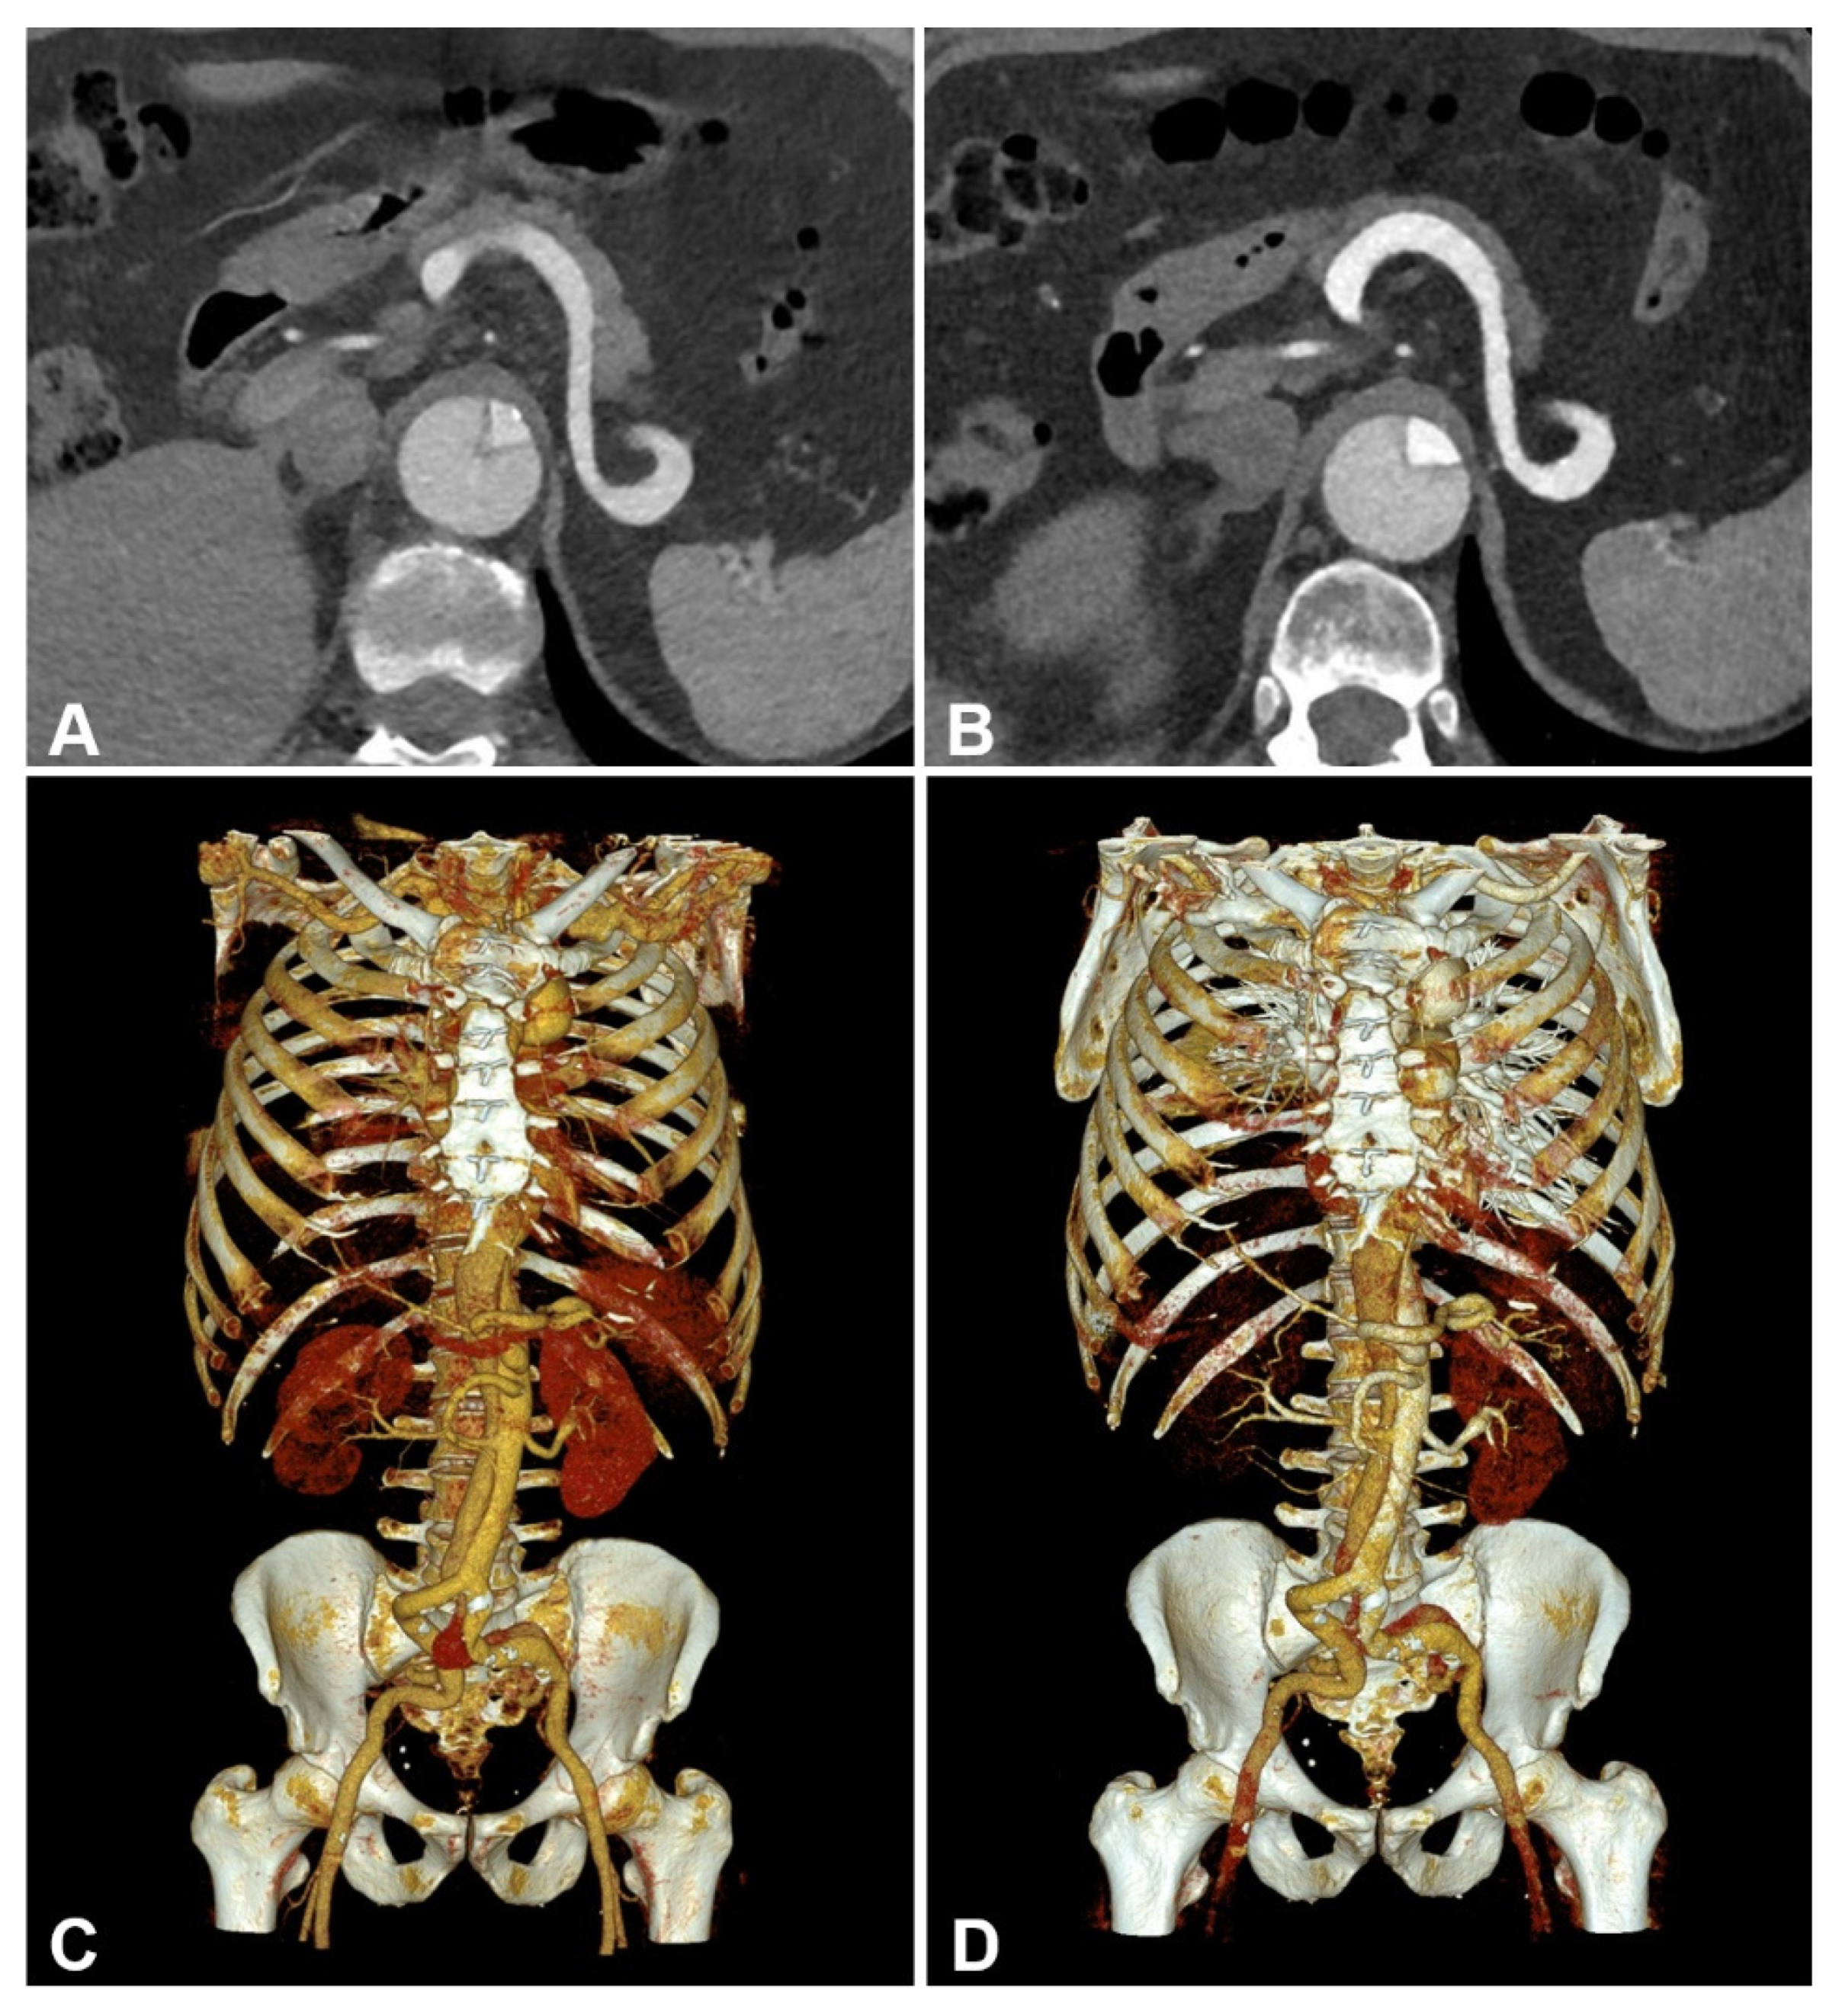

3.2. Objective Image Quality

3.3. Subjective Image Quality